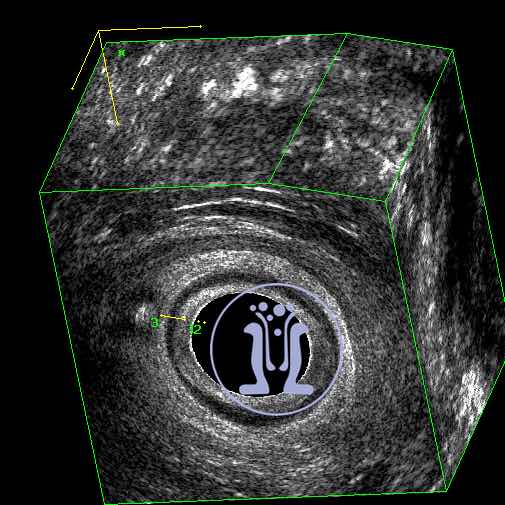

Ασθενής, με ιστορικό σαρκοείδωσης, προσήλθε με ενόχληση στη καθιστή θέση και εκροή διαυγούς υγρού από 10ημερου. Κατά τη κλινική εξέταση, ανευρέθηκε έξω στόμιο συριγγίου, στην 6η ώρα. Το ενδοπρωκτικό υπερηχογράφημα δείχνει χαμηλό συρίγγιο, το οποίο παίρνει ελάχιστο τμήμα εξω σφικτήρα (0.23mm). Προτείνεται διάνοιξη του συριγγώδους πόρου υπό τοπική αναισθησία, η οποία και πραγματοποιείται επιτυχώς χωρίς περαιτέρω δυσκολίες.